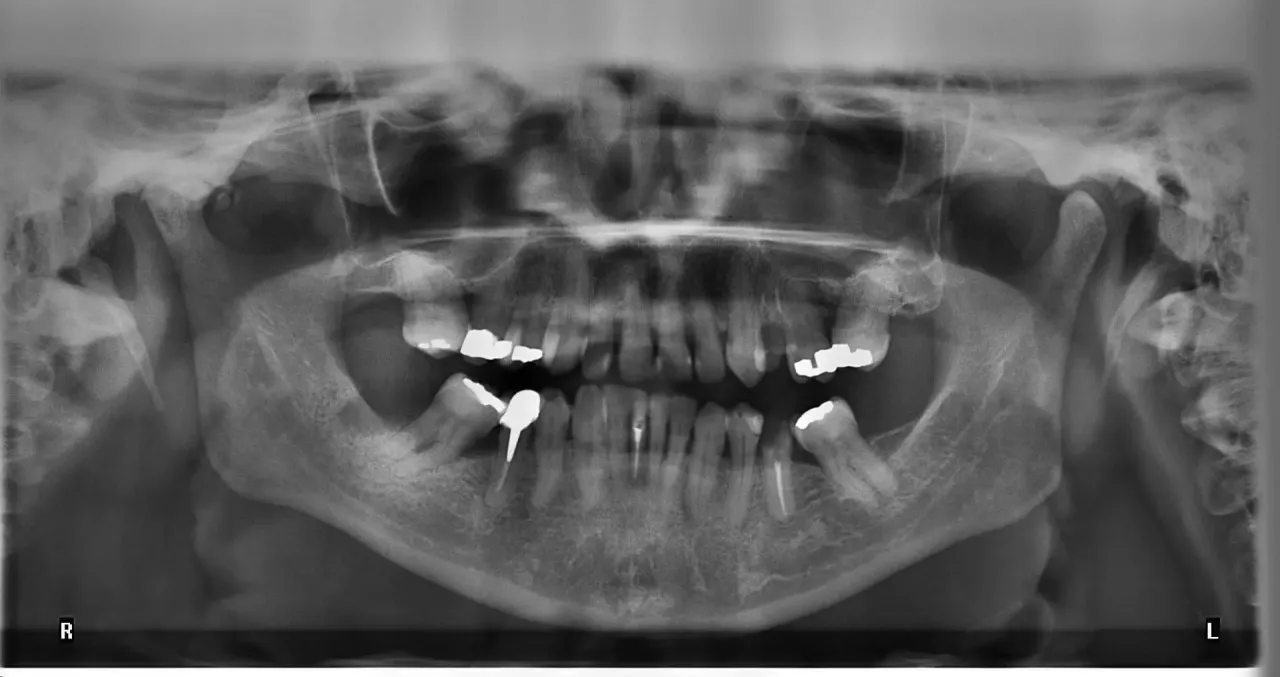

Jak wykorzystać pantomogram w diagnostyce stomatologicznej?

Pantomogram to nie tylko narzędzie diagnostyczne, ale także kluczowy element w planowaniu leczenia stomatologicznego. Dzięki szerszemu obrazowi uzyskanemu z pantomogramu, dentyści mogą dokładniej ocenić stan zębów, kości szczęki oraz tkanek miękkich. Warto zwrócić uwagę, że nowoczesne technologie, takie jak tomografia komputerowa czy zdjęcia 3D, mogą być wykorzystywane w połączeniu z pantomogramem, co pozwala na jeszcze dokładniejszą diagnostykę i lepsze planowanie leczenia, szczególnie w przypadku skomplikowanych przypadków medycznych.